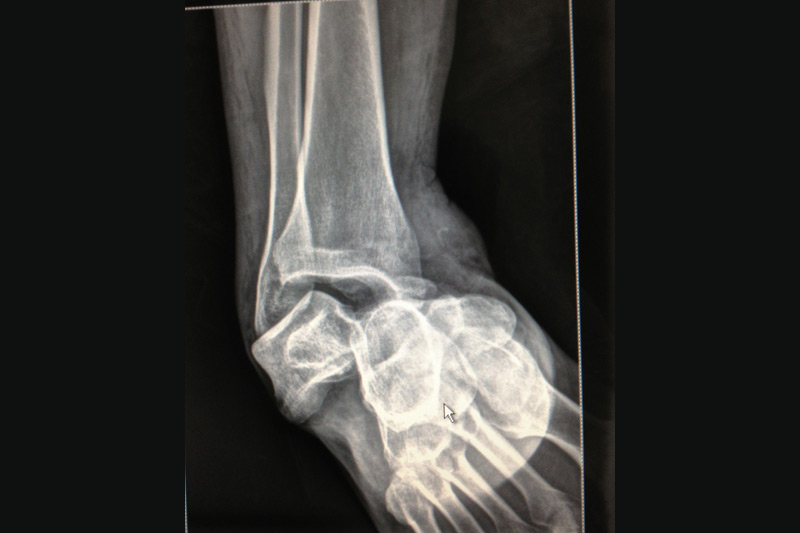

Debido a los accidentes de tránsito, a diario las personas sufren fracturas y lesiones de alto impacto, se otorga manejo de estas lesiones con implantes y material de osteosíntesis restableciendo la anatomía.